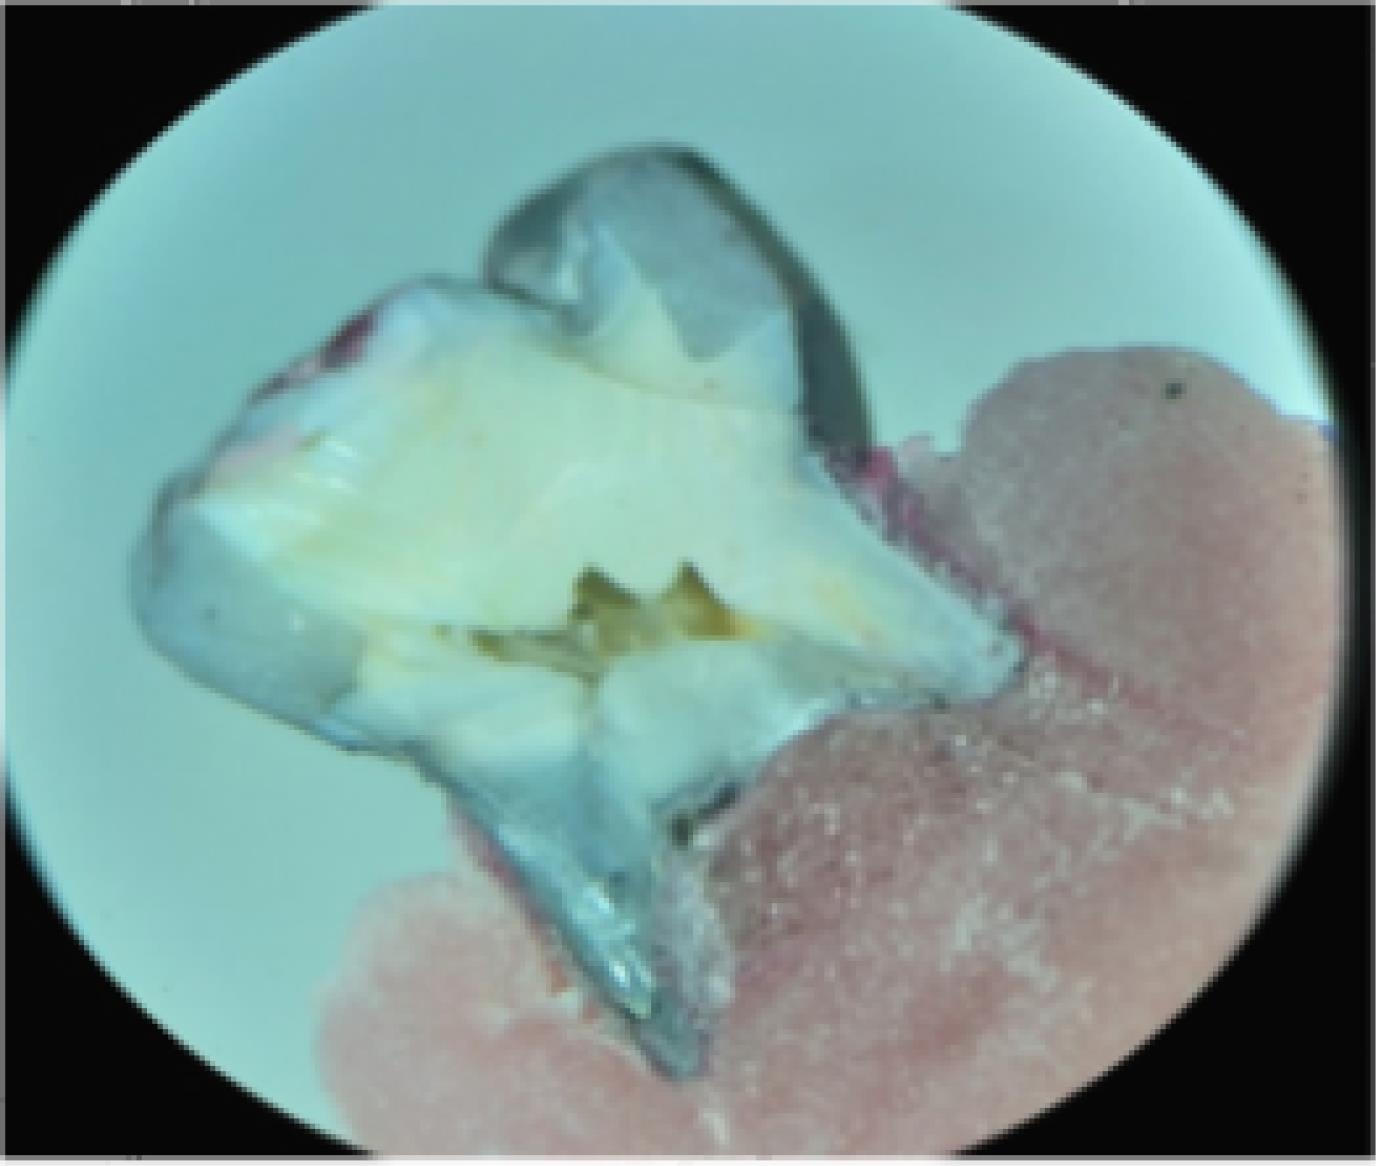

The samples were placed in the radiographic developer solution and then under a fluorescent light for 12 hours, followed by rinsing again with water for 5 minutes. To blind the operators about group allocations, each sample was given a code after the preparation process and before mounting. Next, the samples were mounted in the acrylic resin in such a way that all tooth surfaces were buried in the acrylic resin up to 2 mm lower than the gingival margin of the restorations. Subsequently, the tooth samples were cut longitudinally in the mesiodistal direction from the restoration center using diamond disks (Drux, Germany). Afterward, microleakage was evaluated and imaged under a stereomicroscope (Zistrad, Iran) on the gingival wall at × 40 magnification (Figure 1). After assessing the image, the level of linear penetration was measured and recorded using a microleakage classification method (ISO/TS 11405:2003) (14).

Figure 1.

Sample of an Observed Image by Stereomicroscope